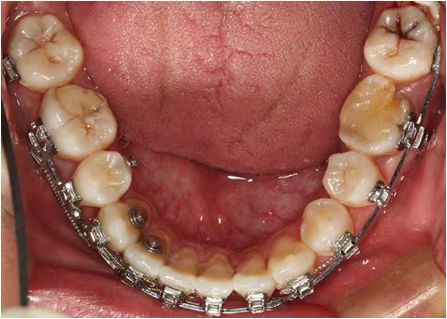

情况:不接受外科手术,在当地做了1年半的矫治,遇到困难无法进行。由外地正畸同行推荐来上海寻求非手术矫治的二手病例。武广增老师接收时的错合畸形情况,呈现严重的骨性反合偏合及侧方开合(图1-图10)。由于推荐其去口腔医院接受正颌外科手术遭到拒绝,武广增老师通过专业的检查、分析,制定一套详细的治疗计划,采用了磨牙推进器技术、武式辅弓技术等特色正畸手段获得明显效果(图2-1~图2-9)。治疗结束后也拍摄了相关照片(图3-1~图3-9)。

矫治前

图1